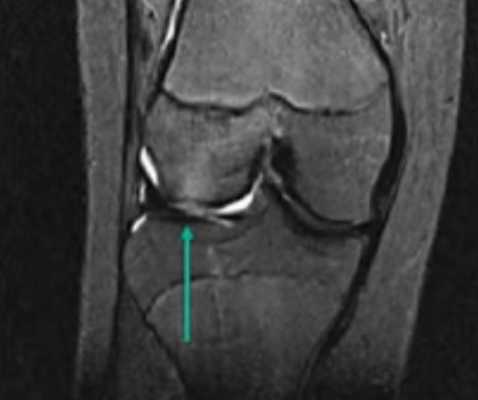

МР-изображение субхондрального перелома латерального мыщелка (зона повреждения указана стрелкой)

Явление ядерно-магнитного резонанса позволяет досконально изучить мягкие ткани. Кости на снимках видны недостаточно хорошо (по сравнению с КТ или рентгеном). Что дает МРТ коленного сустава? Исследование помогает выяснить сведения об окружающих сочленение структурах, по состоянию которых определяют скрытые (субхондральные) переломы: их нельзя или крайне трудно увидеть при рентгенографии. Полипроекционность, высокая разрешающая способность и возможность использования разных режимов сканирования — преимущества МРТ перед другими методами.

Субхондральный перелом латерального мыщелка на МРТ (указан стрелками)